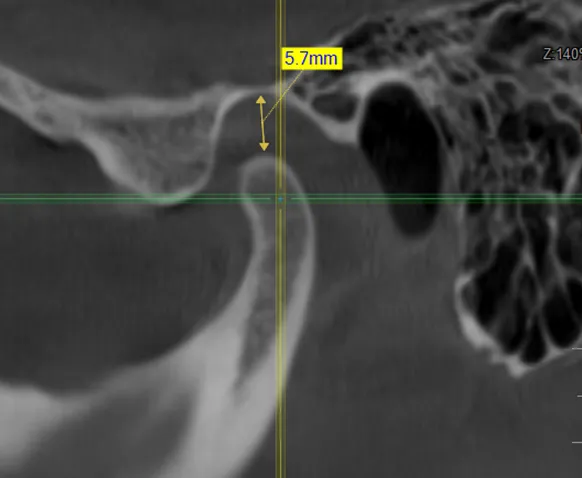

• компьютерная томография (КТ),